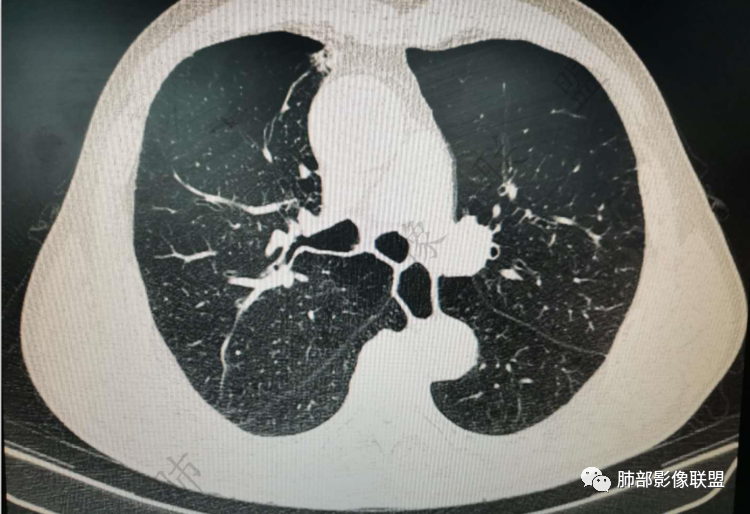

右肺上类圆形叶结节,周边见细软毛刺,增强后呈环形明显强化,内部坏死,邻近胸膜光滑,结合病史2个月明显增大,考虑炎性可能性大。

老年男性,炎性指标略高,肺气肿背景。右肺上叶胸膜下结节,部分边缘平直,部分稍模糊,软长毛刺,血管增粗,病灶中心密度减低,邻近脂肪间隙清晰。考虑炎性肉芽肿或慢性炎症,鉴别鳞癌。

老年男性,炎性指标略高,肺气肿背景。右肺上叶胸膜下结节,部分边缘平直,部分稍膨隆,供血血管增粗,增强扫描病灶中心密度减低,呈环形强化,邻近脂肪间隙清晰。考虑炎性肉芽肿或慢性炎症,鉴别鳞癌。

右肺上叶前段胸膜下结节,边缘分叶毛刺,血管集束,支气管截断,纵膈胸膜牵拉,内乳动脉增粗,密度不均,中央可见坏死,两个月短期随访结节有增大,考虑恶性,腺癌。鉴别结核。

肺气肿背景,右肺上叶纵隔旁胸膜下结节,有血管集束,支气管堵塞,内乳动脉增粗,增强不均匀强化,内可见低密度区。考虑为恶性可能性大

老年男性,肺气肿背景,右肺上叶胸膜下弧立实性不规则结节,密度不均,其内低密度坏死影,支气管似有截断,血管集束,2月复查明显增大,考虑恶性,鳞癌可能大,鉴别炎性肉芽肿

老年男性,炎性指标略高。影像表现右肺上叶胸膜下结节,膨胀性生长部分边缘平直,边界清晰,病灶可见血管集束征,近段支气管阻断?增强扫描病灶中心密度减低,低密度区边界模糊,外围环形强化。老年性,不能排除恶性病变,周围性鳞癌,其次才考虑炎性肉芽肿或慢性炎症

右上叶前段结节,肺气肿背景,血管滋养丶支气管截断,与纵隔脂肪间隙清析

老年男性,肺气肿背景,右肺上叶前段胸膜下结节,部分边缘毛糙,血管集束增粗,支气管似有截断,胸膜牵拉,结节密度不均,两个月随访结节有增大,考虑恶性,肺癌可能;另右肺上叶后段肋胸膜区小片状类结节影,考虑炎性可能。

右肺上叶前段胸膜下结节,近段支气管截断,血管伸入结节内,密度不均,同侧临近内乳动脉增粗,不均匀强化,肺气肿背景,两月明显增大,考虑低分化鳞癌,隐球菌代排

老年男性,白细胞计数及CRP稍高,右肺上叶结节,两个月来有增大,部分边缘可见边界模糊的GGO,局部边缘平直、凹陷,临近胸膜增厚,内见坏死,坏死区边界未见明显壁结节,壁较厚而且均匀强化,支气管似乎有扩张然后截断,近端血管增粗明显。考虑炎性病变,脓肿?有结核病人密切接触史,注意是否为结核。有点难以理解的是为什么右侧内乳动脉增粗明显。

老年男性,无症状,炎性指标增高。肺气肿背景,右肺上叶前段结节,边缘部分平直部分澎隆,血管集束,支气管至病变边缘似截断,近端扩张。增强环形强化,中心坏死。两月内病灶增长太快,考虑炎性肉芽肿,慢性脓肿?结核?癌待排。

肺气肿背景

支气管变形、壁增厚,提示慢性支气管炎症

边缘平直

宽基底与胸膜相连,附近胸膜增厚,糊墙

内乳动脉关系似乎不密切

内部有低强化区,边界尚清

还是支持炎性放前面,恶性待排